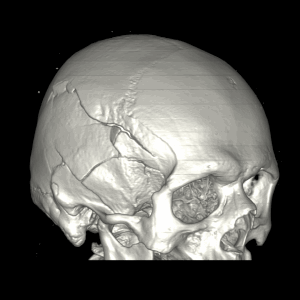

ПЕРЕЛОМЫ ЧЕРЕПА НА КТ

Изменения костей черепа травматического характера четко и достоверно выявляются при компьютерной томографии головы: можно оценить характер перелома, направление линий перелома, глубину импрессии (вдавления костных отломков), количество костных отломков, их размеры, форму, положение.

Перелом правой лобной кости на КТ. Виден вдавленный перелом свода черепа, воздух в эпидуральном пространстве.

Трехмерная реконструкция черепа при КТ визуализирует сложный перелом правой височно-теменной области.